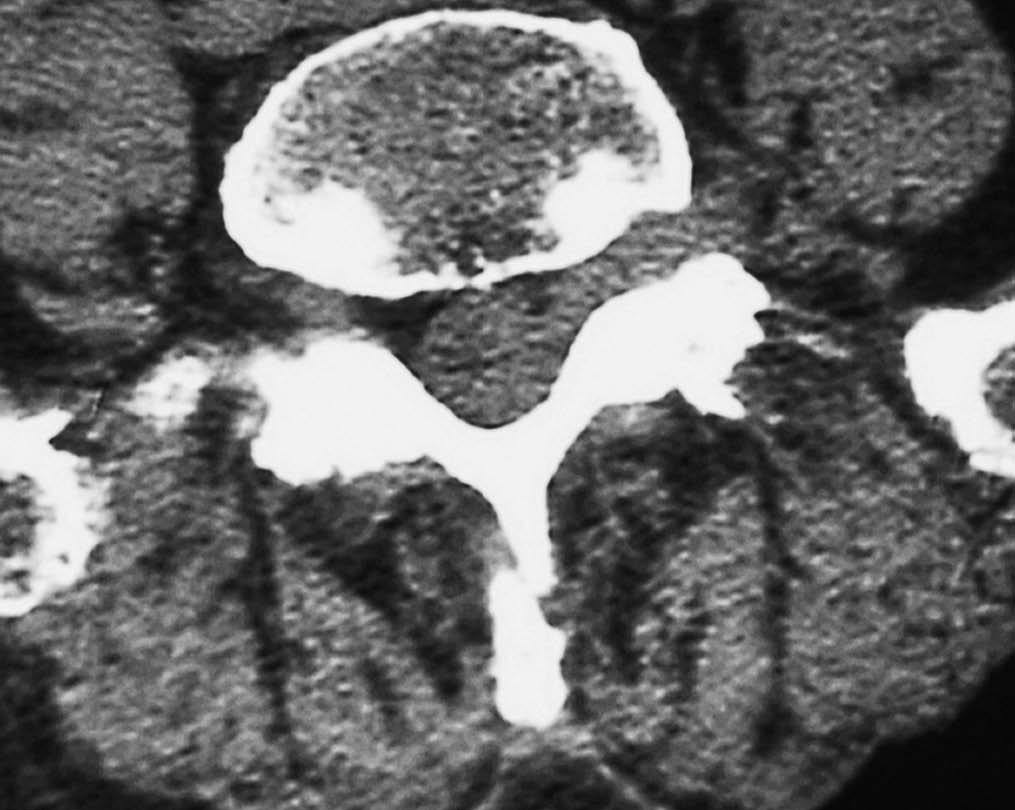

Fig. 2--TC sin contraste. Corte axial. Lesión en margen lateral del canal, foramina y espacio extraforaminal, con pequeña burbuja de gas en su interior. No se aprecian erosiones óseas.